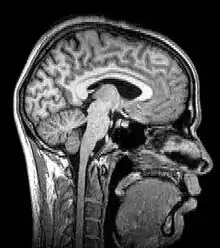

Sagittal MRI slice at the midline

Magnetic resonance imaging (MRI) uses magnetic fields and radio waves to produce high quality two- or three-dimensional images of brain structures without the use of ionizing radiation (X-rays) or radioactive tracers.

The record for the highest spatial resolution of a whole intact brain (postmortem) is 100 microns, from Massachusetts General Hospital. The data was published in Scientific Data on 30 October 2019.[13]